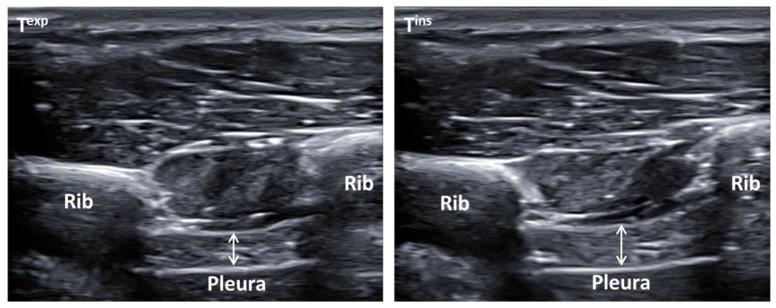

The aim of the present study was to determine the gender respiratory differences of bilateral diaphragm thickness, respiratory pressures, and pulmonary function in patients with low back pain (LBP). A sample of 90 participants with nonspecific LBP was recruited and matched paired by sex (45 women and 45 men). Respiratory outcomes included bilateral diaphragm thickness by ultrasonography, respiratory muscle strength by maximum inspiratory (MIP) and expiratory (MEP) pressures, and pulmonary function by forced expiratory volume during 1 s (FEV), forced vital capacity (FVC) and FEV/FVC spirometry parameters. The comparison of respiratory outcomes presented significant differences ( < 0.001), with a large effect size ( = 1.26-1.58) showing means differences (95% CI) for MIP of -32.26 (-42.99, -21.53) cm HO, MEP of -50.66 (-64.08, -37.25) cm HO, FEV of -0.92 (-1.18, -0.65) L, and FVC of -1.00 (-1.32, -0.69) L, with lower values for females versus males. Gender-based respiratory differences were presented for maximum respiratory pressures and pulmonary function in patients with nonspecific LBP. Women presented greater inspiratory and expiratory muscle weakness as well as worse lung function, although these differences were not linked to diaphragm thickness during normal breathing.

本研究旨在确定患有下背痛(LBP)患者的双侧膈肌厚度、呼吸压力和肺功能的性别呼吸差异。招募了 90 名非特异性 LBP 患者作为样本,并按性别(45 名女性和 45 名男性)进行配对。呼吸结果包括超声检查的双侧膈肌厚度、最大吸气(MIP)和呼气(MEP)压力的呼吸肌力量,以及 1 秒用力呼气量(FEV)、用力肺活量(FVC)和 FEV/FVC 肺活量计参数的肺功能。呼吸结果的比较显示出显著差异(<0.001),具有较大的效应量(=1.26-1.58),表明 MIP 的平均差异(95%CI)为-32.26(-42.99,-21.53)cmH2O,MEP 为-50.66(-64.08,-37.25)cmH2O,FEV 为-0.92(-1.18,-0.65)L,FVC 为-1.00(-1.32,-0.69)L,女性的数值低于男性。非特异性 LBP 患者的最大呼吸压力和肺功能存在基于性别的呼吸差异。女性表现出更大的吸气和呼气肌肉无力以及更差的肺功能,尽管这些差异与正常呼吸时的膈肌厚度无关。